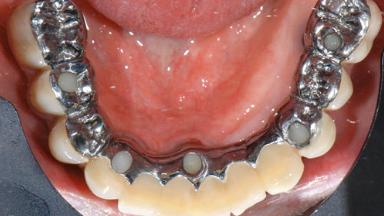

A 77-year-old male patient was referred for the management of frequent and repeated acrylic fracture of his existing mandibular fixed full-arch implant-supported metal/acrylic prosthesis. He also complained about softtissue soreness and the lack of retention and stability of his maxillary removable partial metal/acrylic prosthesis. Both prostheses had been delivered two years previously as part of his full-mouth rehabilitation (caries, tooth wear, tooth fracture). His medical history revealed high blood pressure, controlled with the use of antihypertensive medication.